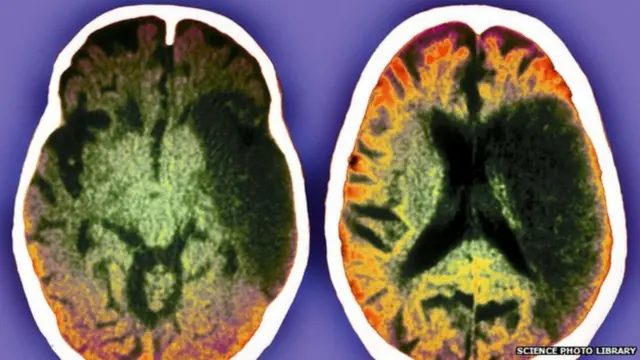

ਤਸਵੀਰ ਸਰੋਤ, science photo library

ਮਾਹਰਾਂ ਮੁਤਾਬਕ ਜਿੰਨੀ ਜਲਦੀ ਹੋ ਸਕੇ, ਐਂਬੂਲੈਂਸ ਬੁਲਾਉਣੀ ਚਾਹੀਦੀ ਹੈ। ਮਰੀਜ਼ ਨੂੰ ਖ਼ੁਦ ਹਸਪਤਾਲ ਨਾ ਲੈ ਕੇ ਜਾਓ। ਤੁਰੰਤ ਇਲਾਜ ਲਈ ਐਂਬੂਲੈਂਸ ਬੁਲਾਉਣੀ ਚਾਹੀਦੀ ਹੈ।

ਹੇਲੀ ਸ਼ਾਹ ਨੇ ਬੀਬੀਸੀ ਨੂੰ ਦੱਸਿਆ, “ਜੇਕਰ ਦਿਮਾਗ ਨੂੰ ਖੂਨ ਦੀ ਸਪਲਾਈ ਵਿੱਚ ਰੁਕਾਵਟ ਹੋਣ ਦਾ ਤੁਰੰਤ ਇਲਾਜ ਨਾ ਕੀਤਾ ਜਾਵੇ, ਤਾਂ ਹਰ ਸਕਿੰਟ ਦਿਮਾਗ ਦੇ 32,000 ਸੈੱਲ ਮਰ ਜਾਂਦੇ ਹਨ।”

“ਜੇਕਰ ਸਟ੍ਰੋਕ ਦੇ ਪਹਿਲੇ ਤਿੰਨ ਘੰਟਿਆਂ ਦੇ ਅੰਦਰ ਟੀ.ਪੀ.ਏ. ਨਾਮ ਦਾ ਟੀਕਾ ਲਗਾਇਆ ਜਾਂਦਾ ਹੈ, ਤਾਂ ਸਟ੍ਰੋਕ ਦਾ ਖਤਰਾ ਕਾਫ਼ੀ ਘੱਟ ਹੋ ਸਕਦਾ ਹੈ ਅਤੇ ਇਸ ਦੇ ਪ੍ਰਭਾਵ ਨੂੰ ਘਟਾਇਆ ਜਾ ਸਕਦਾ ਹੈ।”

“ਇਸ ਤੋਂ ਇਲਾਵਾ ਖੂਨ ਨੂੰ ਪਤਲਾ ਕਰਨ ਵਾਲੀਆਂ ਦਵਾਈਆਂ, ਦਿਮਾਗ ਦੇ ਸੈੱਲਾਂ ਦੀ ਸੁਰੱਖਿਆ ਲਈ ਦਵਾਈਆਂ, ਲੋੜ ਅਨੁਸਾਰ ਸਰਜਰੀ ਅਤੇ ਢੁਕਵੀਂ ਕਸਰਤ ਵੀ ਸਟ੍ਰੋਕ ਦੀ ਗੰਭੀਰਤਾ ਨੂੰ ਘਟਾ ਸਕਦੀ ਹੈ।”

ਇਹ ਟੀਕਾ ਦਿਮਾਗ ਦੇ ਖਰਾਬ ਹੋਏ ਖੇਤਰ ਵਿੱਚ ਖੂਨ ਦੇ ਪ੍ਰਵਾਹ ਨੂੰ ਬਹਾਲ ਕਰਨ ਵਿੱਚ ਮਦਦ ਕਰਦਾ ਹੈ।

ਜੇਕਰ ਮਰੀਜ਼ ਨੂੰ ਸਟ੍ਰੋਕ ਹੋਇਆ ਹੈ, ਤਾਂ ਡਾਕਟਰ ਤੁਰੰਤ ਸੀਟੀ ਸਕੈਨ ਜਾਂ ਐੱਮਆਰਆਈ ਕਰਾਉਣ ਲਈ ਕਹੇਗਾ।